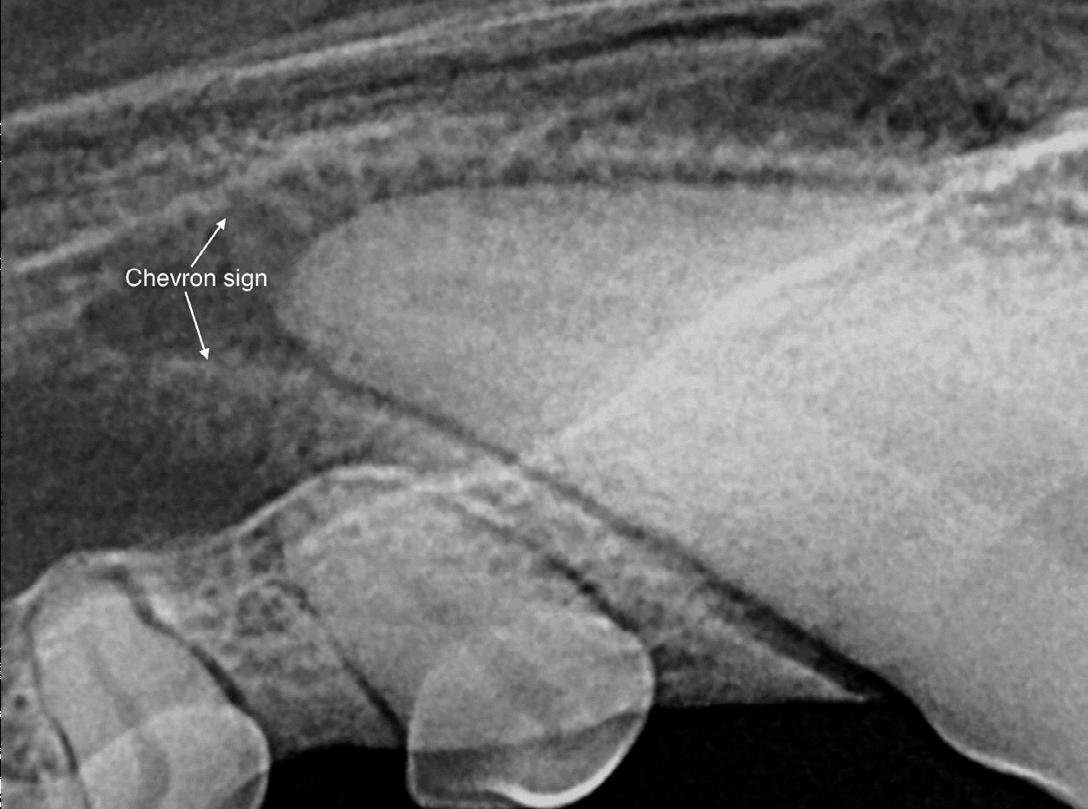

These radiograph abnormalities should not be confused with chevron signs or chevron effects. To differentiate this artifact from true endodontic pathology, evaluate the periodontal ligament space and lamina dura around the root apex. Generally, periapical lesions of endodontic origin will appear more circular on radiographs compared with chevron-shaped lucencies. Additionally, there should be a visible loss of the radiolucent continuity of the periodontal ligament space and radiodensity of the dura with endodontic disease.

Figure 8: Cheveron sign apparent on right maxillary canine apex radiograph. Image courtesy of Dr. Jan Bellows. Figure 9A: Stage 2 external root resorption affecting a cat’s right mandibular canine. Image courtesy of Dr. Jan Bellows. Figure 9B: Stage 3 external root resorption affecting a cat’s left maxillary canine tooth. Image courtesy of Dr. Jan Bellows.